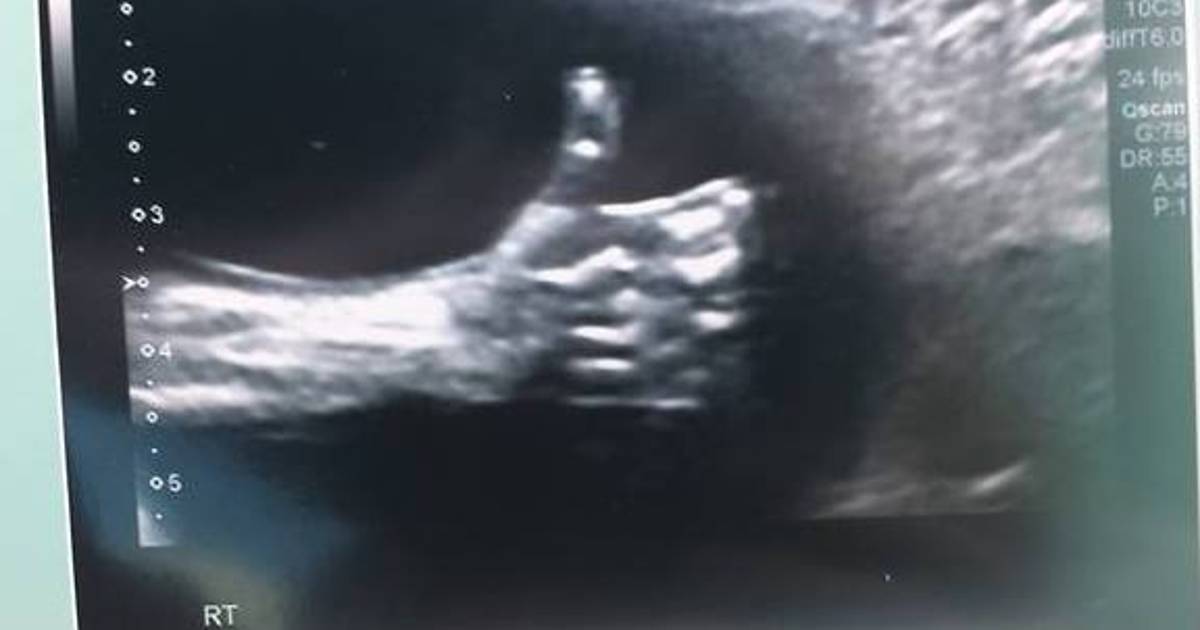

Nicole Kim, la madre, encontró este inspirador mensaje en la ecografía de la semana 20: un pulgar para arriba

Nicole Kim, la madre, encontró este inspirador mensaje en la ecografía de la semana 20: un pulgar para arriba. Kim contó en la web del programa Today, de la NBC, que el mensaje del bebé llegó justo cuando su padre, Tony, lo acababan de echar del trabajo.

En una entrevista con el Calgary Herald, Kim contó también que el técnico de la clínica de Calgary donde hizo la ecografía le dio rápidamente al zoom y tomó la foto cuando vio al bebé con el pulgar levantado.